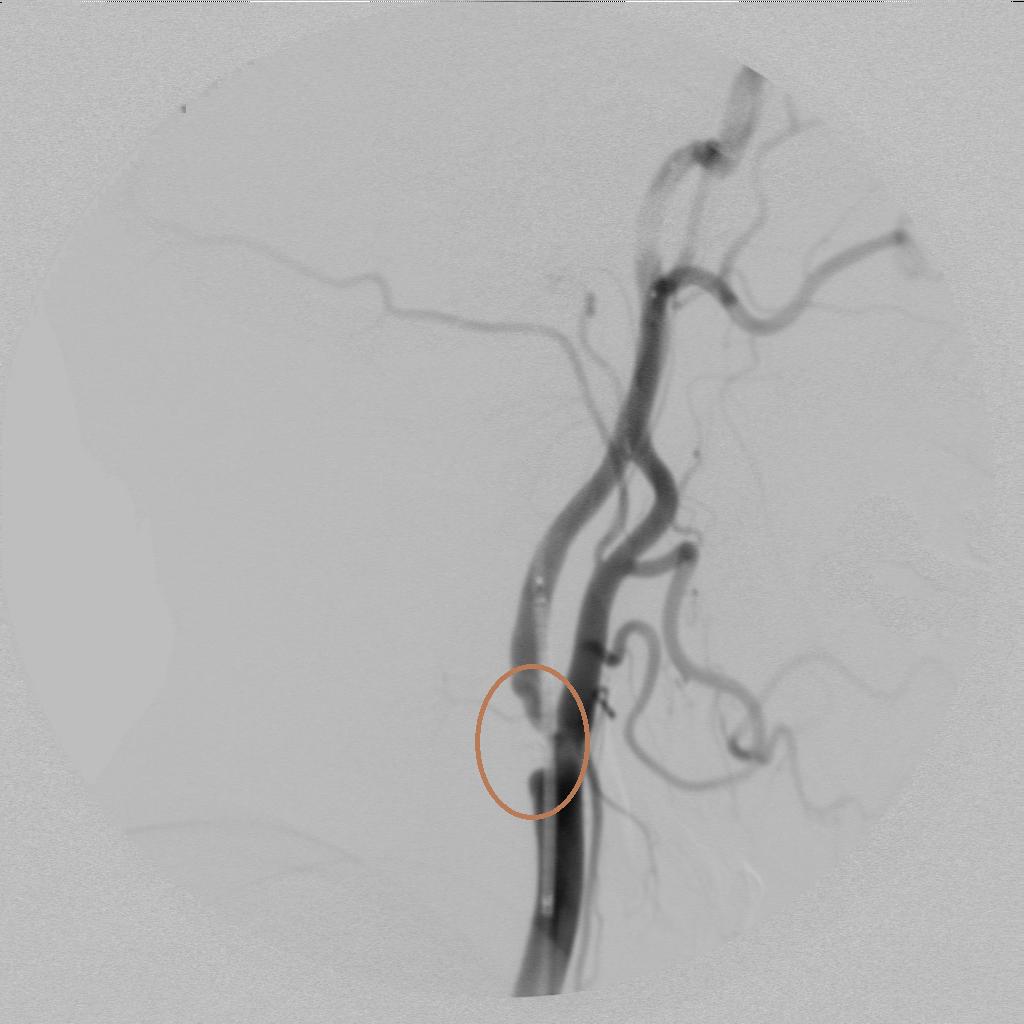

术中进行血管再通治疗